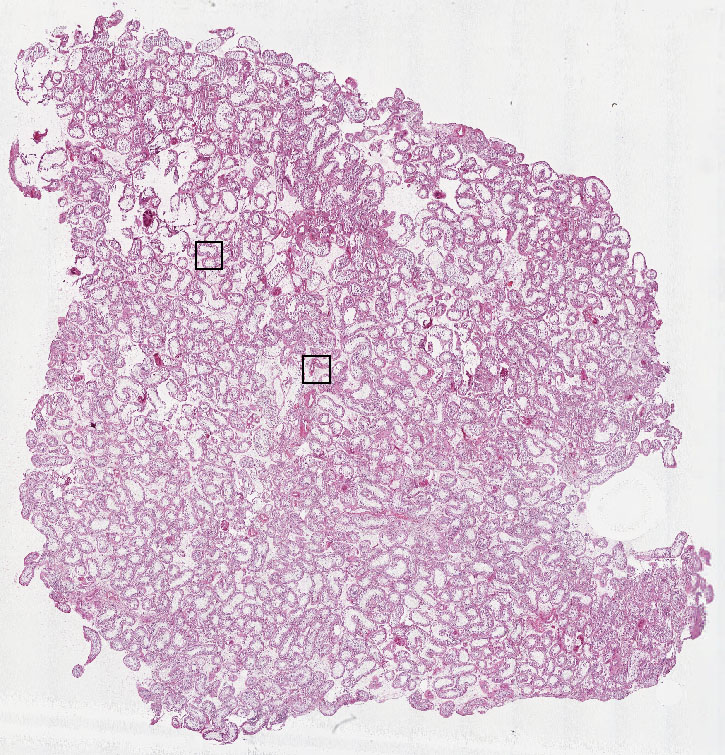

Cells in seminiferous ducts:

65

Other cell types:

35